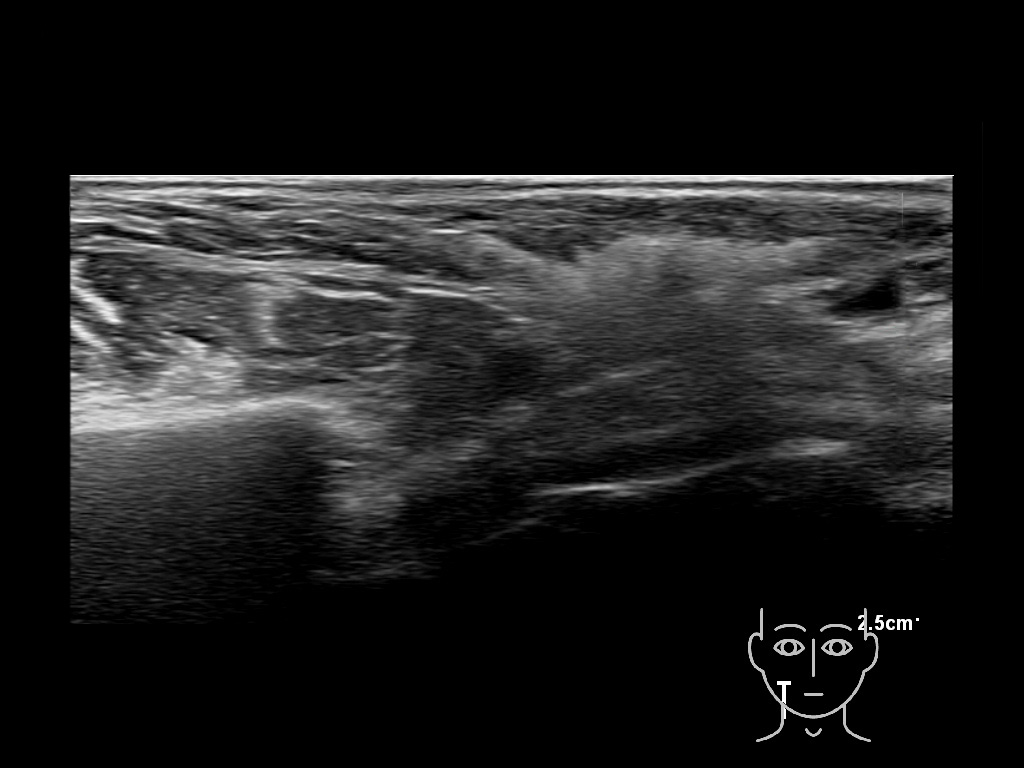

haca 0

HAca 10a